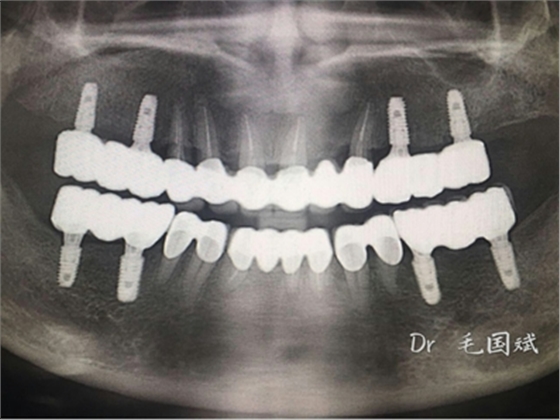

毛國(guó)斌種植病例——群討論分享